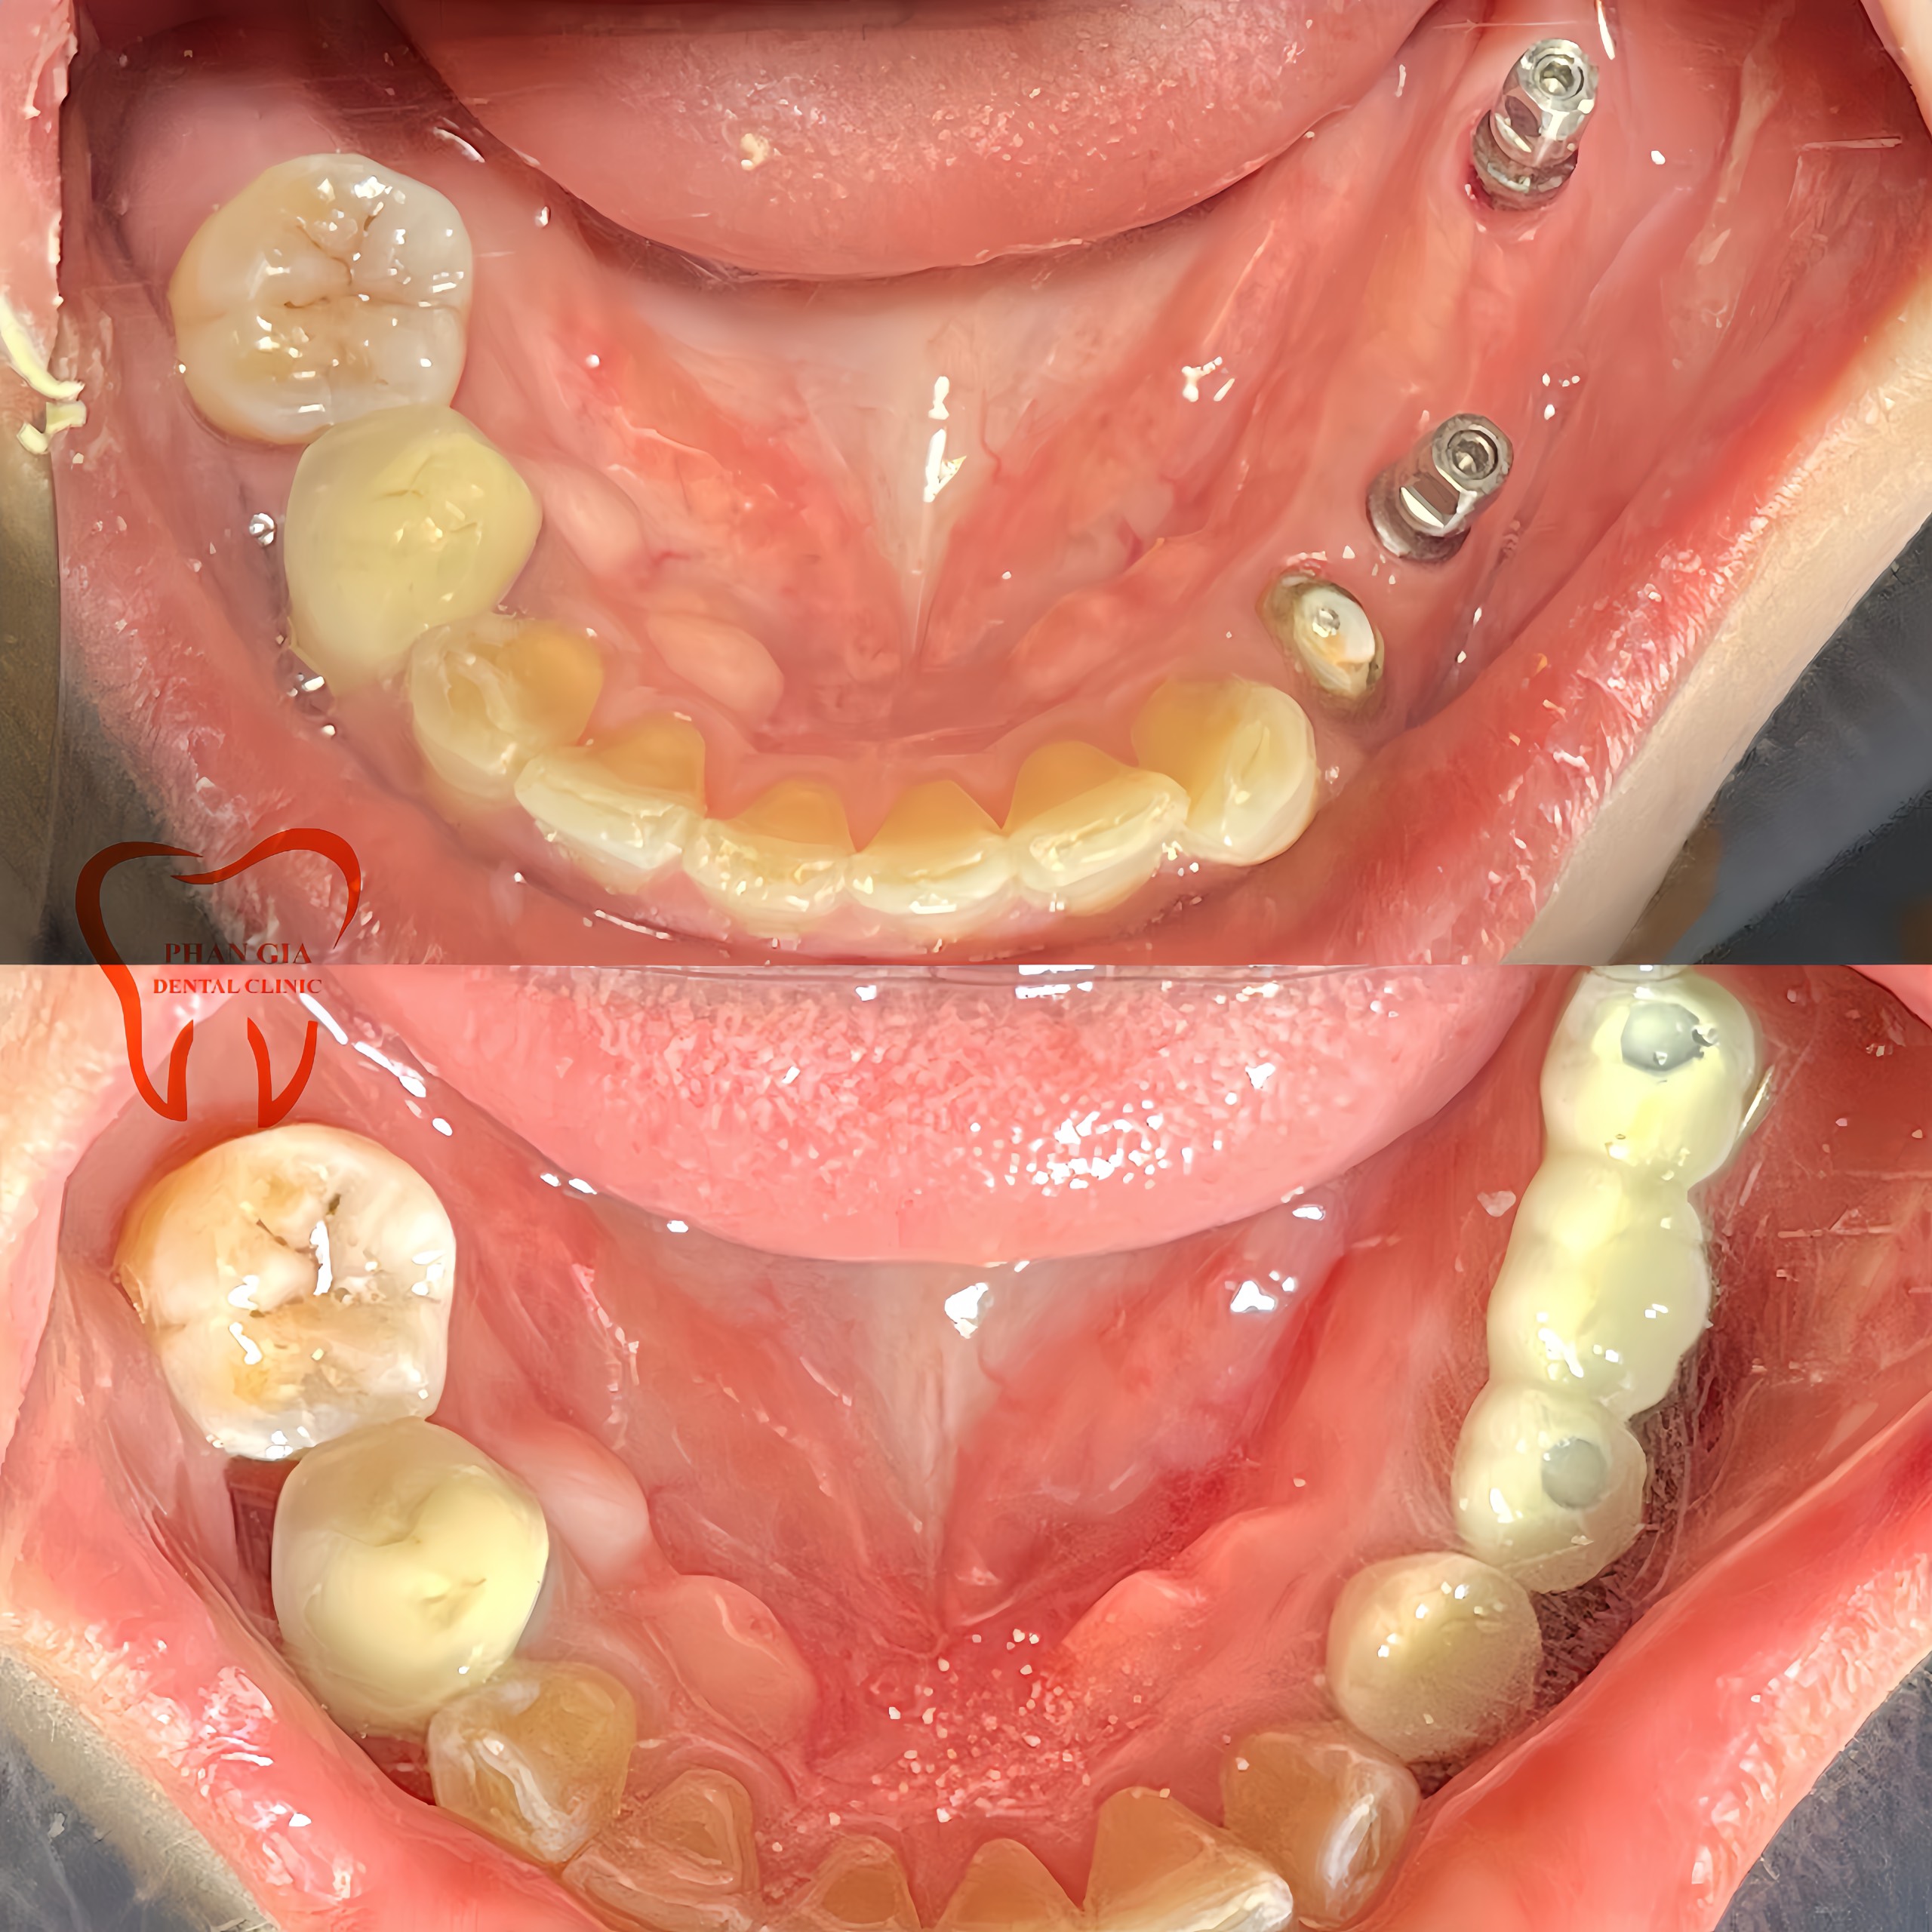

Chú QUỐC PHÙ đến với PHAN GIA trong tình trạng răng bị lung lay đã phải nhổ bỏ hết hàm . Với nhu cầu làm hàm tháo lắp nhưng do lần đầu sử dụng hàm tháo lắp nên không quen, khó ăn nhai,cảm giác nhai không thật… Muốn vừa tiện vừa tiết kiệm cho chú bác sĩ đã tư vấn chú cắm 2 trụ implant để làm bệ đở vừa sử dụng được hàm tháo lắp vừa giúp giữ vững hàm tháo lắp hơn, ăn nhai mạnh dạn và lực nay cũng tốt hơn.

Chú Q một case viêm nha chu vùng răng cối phân hàm 2 và 4 gây tụt nướu lộ chân răng, răng lung lay nhiều bắt buột phải nhổ bỏ . Khi nhổ đi dĩ nhiên không còn răng ăn nhai nữa, với tư tưởng không đeo hàn tháo lắp, muốn lựa chọn phương pháp phục hình cố định chú đã chốt đơn 6 trụ implant để làm lại răng đã mất phục hồi lại chức năng ăn nhai của răng hàm.

Khách hàng Việt Hồng, trường hợp chị Hồng trước đây bị răng sâu vỡ lớn không thể giữ lại và 1 số R bị viêm nha chu, tụt nướu lộ chân R bắt buột phải nhổ. Bác sĩ tư vấn chị nên trồng lại các răng đã bị mất để có thể ăn nhai thoải mái trở lại do răng hàm trên của chị vẫn còn và chị vẫn còn trẻ.

Đặt hết niềm tin vào trình độ và tay nghề của đội ngũ Bác sĩ tại PHAN GIA chị quyết định lựa chịn cắm mỗi bên phân hàm 2 trụ implant rồi làm răng sứ lên đó để có răng ăn nhai trở lại.